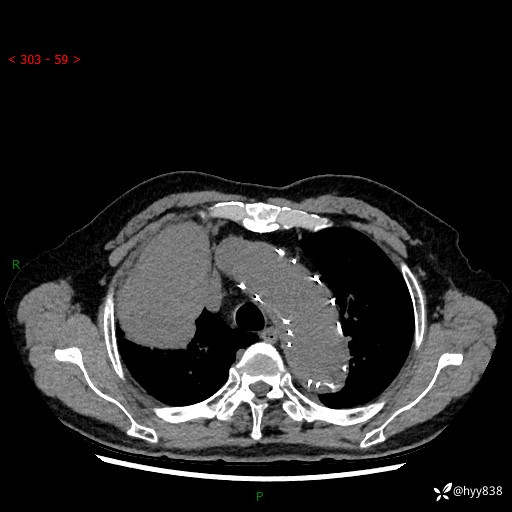

辅助检查:CT

增强动脉期

静脉期